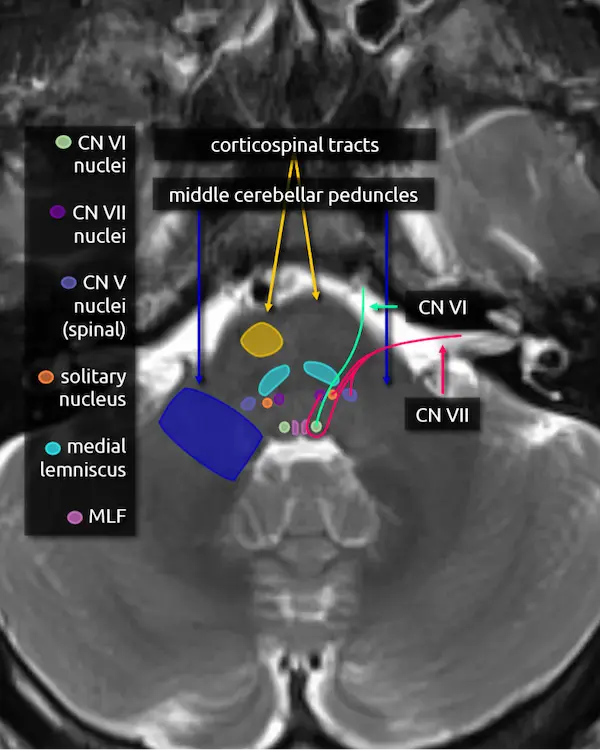

1. Corticospinal tracts

2. Middle cerebellar peduncles

3. Medial lemniscus

4. Medial longitudinal fasciculus (MLF)

5. Abducens nucleus (CN VI)

The abducens nucleus is located in the dorsal pons at the level of the internal auditory canals. The facial colliculi are the two bumps along the dorsal surface of the pons at this level, which are formed by the facial nerve coursing over the abducens nucleus.

Absence of the abducens nucleus occurs in horizontal gaze palsy with progressive scoliosis (HGPPS), which results in an abnormal contour of the posterior pons due to flattening of the facial colliculi.

6. Abducens nerve (CN VI)

The abducens nerve courses anteriorly from the abducens nucleus and exits the ventral pons at the pontomedullary junction. After traversing the prepontine cistern, the nerve enters Dorello's canal, where it is relatively fixed in place. It also has the longest subarachnoid course of the cranial nerves. These two features make it particularly susceptible to stretching-related injury, e.g., in the setting of brain herniation. After Dorello's canal, the nerve enters the cavernous sinus, where it is susceptible to mass effect from space occupying lesions, e.g., a mass or a cavernous internal carotid artery aneurysm.

The abducens nerve innervates the ipsilateral lateral rectus muscle, responsible for eye abduction. Damage will cause horizontal diplopia.

7. Facial nucleus (CN VII)

The facial nucleus is located in dorsal pons anterior to the abducens nucleus and posterior to the medial lemniscus.

8. Solitary nucleus

The solitary nucleus is located lateral to the facial nucleus in the lower pons and extends to the upper medulla. It contributes to the facial, glossopharyngeal, and vagus nerves.

Damage to the solitary nucleus may manifest as decreased taste sensation on the ipsilateral tongue.

9. Spinal nucleus of the trigeminal nerve (CN V)

The spinal nucleus of the trigeminal nerve is the inferior continuation of the main sensory nucleus of the trigeminal nerve (see level 3). It is involved in sensation of the head and face. It receives afferent fibers from the facial, glossopharyngeal, and vagus nerves.

10. Facial nerve (CN VII)

The facial nerve courses posteriorly from the facial nucleus before looping over the ipsilateral abducens nucleus and exiting the anterolateral pons at the pontomedullary junction. It then enters the internal auditory canal with the vestibulocochlear nerve (CN VIII). Four nuclei contribute to the facial nerve; the three listed above, and a fourth called the superior salivary nucleus responsible for parasympathetic fibers located medial to the facial nucleus, not pictured here. The nerve has motor, sensory, and parasympathetic functions: